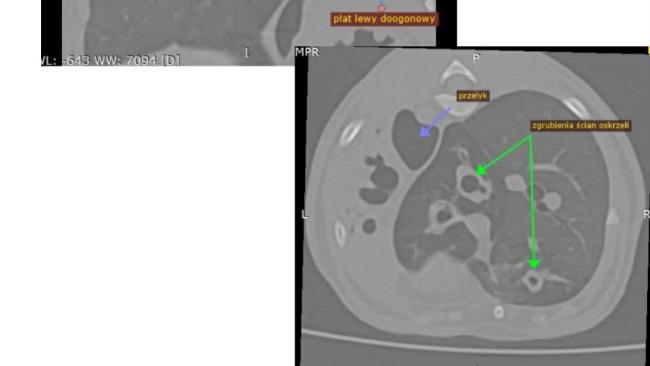

Jak już wiecie nasza mała koteczka Pieczarka czyli Kicisława ma cały czas problemy zdrowotne, nadal nie wiemy co jest ich przyczyną i staramy się robić wszystko aby miała szanse na normalne, długie i szczęśliwie życie.

Wykonalismy tomografię, posiewy, bdania krwi, usg kontrolne, a ostatnio miała punkcję osierdzia iściągnięcie płyku, którego jeszcze tydzień temu nie było, teraz czekamy na wyniki, może wreszcie dowiemy z czym ona i my walczymy.